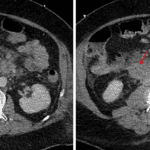

- Hepatomegaly with diffusely decreased attenuation of the hepatic parenchyma

Hepatomegaly with hepatic steatosis.

- Small left greater than right pleural effusions

Small pleural effusions.